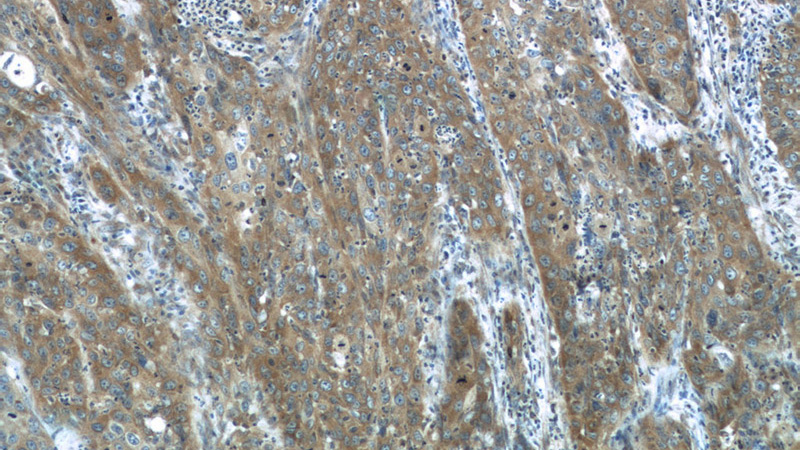

Immunohistochemistry of paraffin-embedded human cervical cancer tissue slide using Catalog No:112696(MMP1 Antibody) at dilution of 1:200 (under 10x lens)